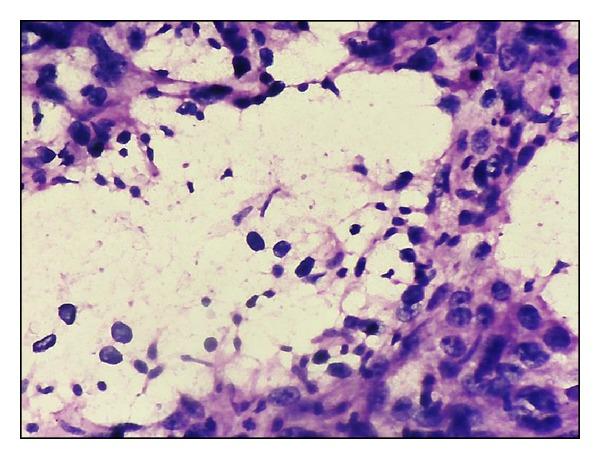

Background. Fine-needle aspiration cytology plays a major role in the primary diagnosis of breast carcinoma. Cytological grading of the smears can provide valuable prognostic information and aid in planning the management options. Aim. To evaluate various 3-tier cytological grading systems and to determine the best possible system which is reliable and objective for use in routine practice. Materials & Methods. 72 fine-needle aspiration smears of breast carcinomas were graded by two pathologists and compared with the histologic grading by Nottingham modification of Scarff-Bloom-Richardson method. Concordance and correlation studies were done. Kappa measurement of interobserver agreement was also done. Results. Robinson's method showed a better correlation (77.7%) and substantial Kappa value of agreement (κ = 0.61) with Bloom Richardson's histological grading method in comparison to the other methods, closely followed by Fisher's method. Fisher's method showed better interobserver agreement (84.7%, κ = 0.616) compared to the other systems. Conclusions. Robinson's method of cytological grading in fine-needle aspiration smears of breast carcinoma is simpler, multifactorial, and feasible, hence being preferable for routine use according to our study.

背景。细针穿刺细胞学检查在乳腺癌的初步诊断中起着重要作用。涂片的细胞学分级可以提供有价值的预后信息,并有助于制定治疗方案。目的。评估各种三级细胞学分级系统,并确定在常规实践中使用的最可靠、客观的最佳系统。材料与方法。由两位病理学家对72例乳腺癌细针穿刺涂片进行分级,并与采用诺丁汉改良的斯卡夫-布卢姆-理查森方法进行的组织学分级进行比较。进行了一致性和相关性研究。还进行了观察者间一致性的kappa测量。结果。与其他方法相比,罗宾逊方法与布卢姆-理查森组织学分级方法显示出更好的相关性(77.7%)和较高的kappa一致性值(κ = 0.61),其次是费舍尔方法。与其他系统相比,费舍尔方法显示出更好的观察者间一致性(84.7%,κ = 0.616)。结论。根据我们的研究,罗宾逊方法用于乳腺癌细针穿刺涂片的细胞学分级更简单、多因素且可行,因此更适合常规使用。